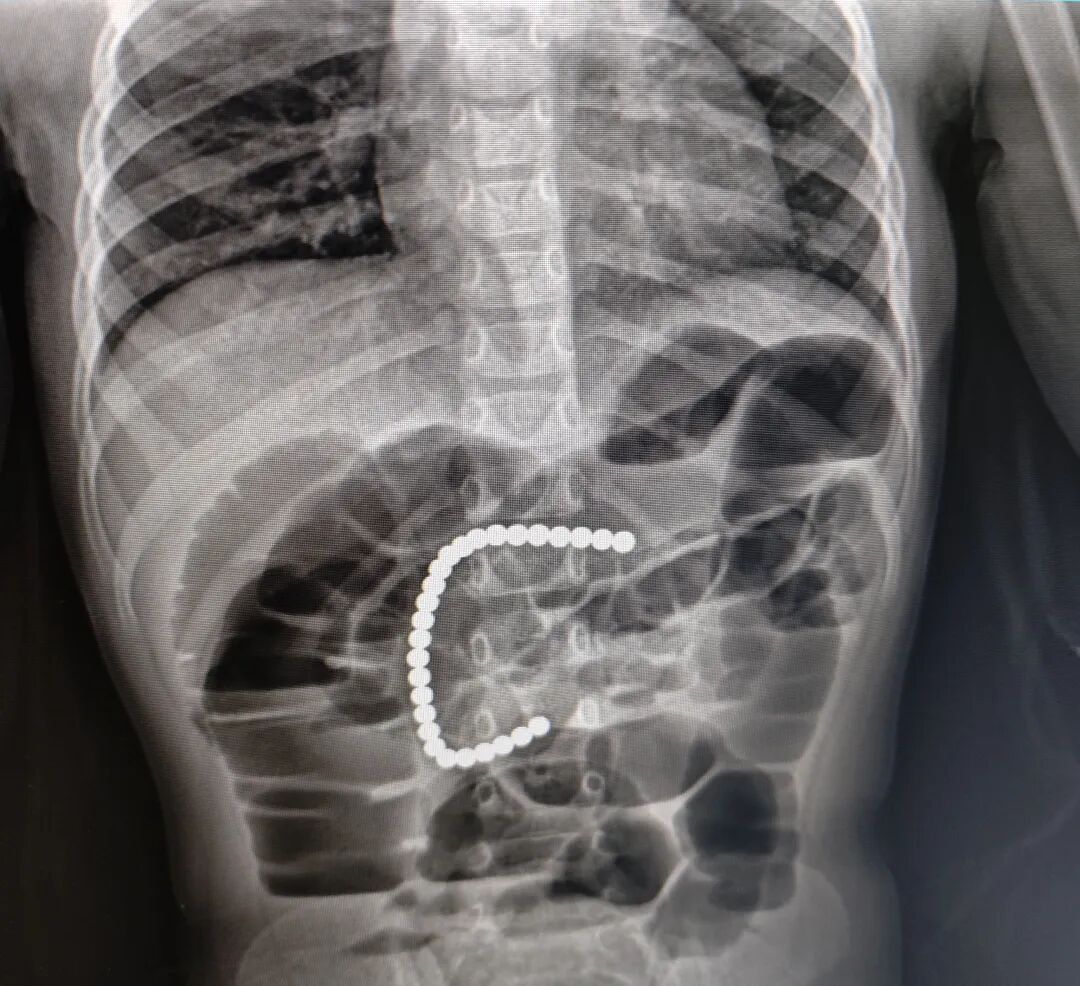

当日19时许,患儿到达医院,李忠赶紧带着患儿去做X光片,患儿磁力珠的位置仍然在胃里。麻醉前需要禁食水,询问患儿了解刚食用晚饭,联系消化内科专家,决定第二日胃镜下取出。

1月26日10时许,李忠带患儿再次拍片,发现磁力珠大部分已到十二指肠,少部分在胃里。按照李忠制定的手术方案,患儿在手术室进行全麻,先由消化内科医生通过胃镜对患儿取磁力珠,如无法取出,李忠将带领医疗团队给予腹腔镜手术,第三个方案则是行开放手术。而患儿这么小,开放手术创伤太大,谁也不想采取第三个方案。